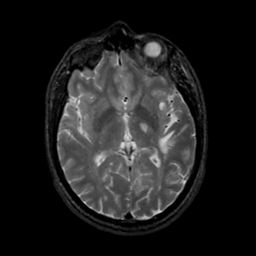

MR Study #17, July 7, 1991 -- Slice #25